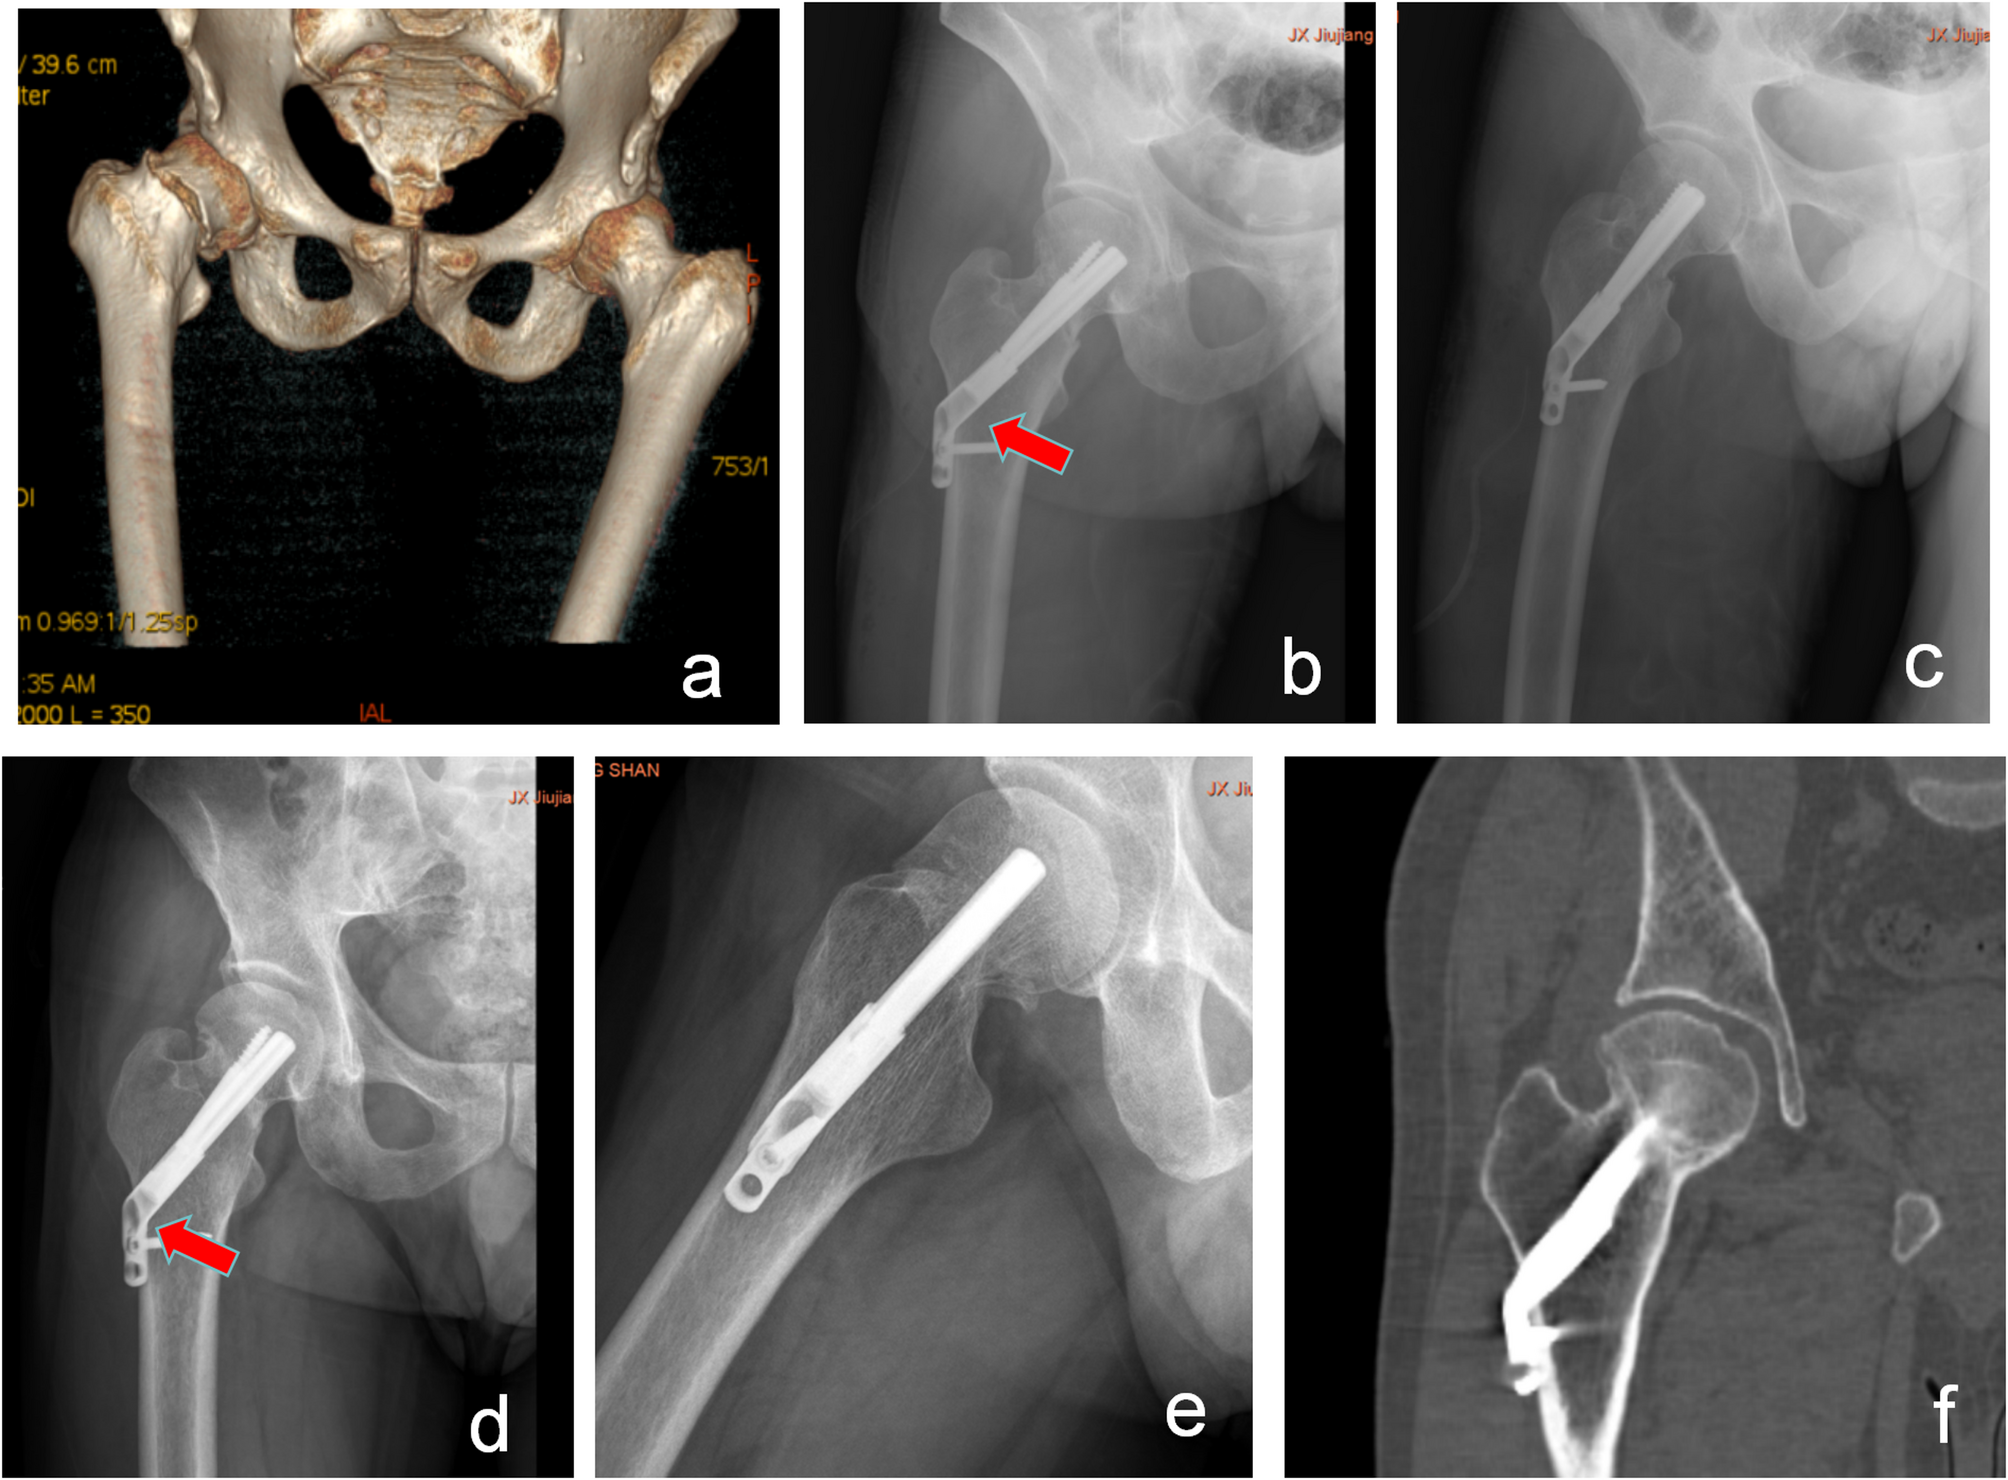

Fig. 4

A 55-year-old male patient with a right femoral neck fracture is classified in the FNS group. (a) Preoperative CT indicates a Pauwels type III right femoral neck fracture. (b,c) Postoperative anteroposterior and lateral X-rays show satisfactory fracture reduction. (d) Eighteen months post-operation, anteroposterior X-rays show fracture healing with femoral neck shortening and slight screw back-out (red arrow). CT confirms the fracture healing.